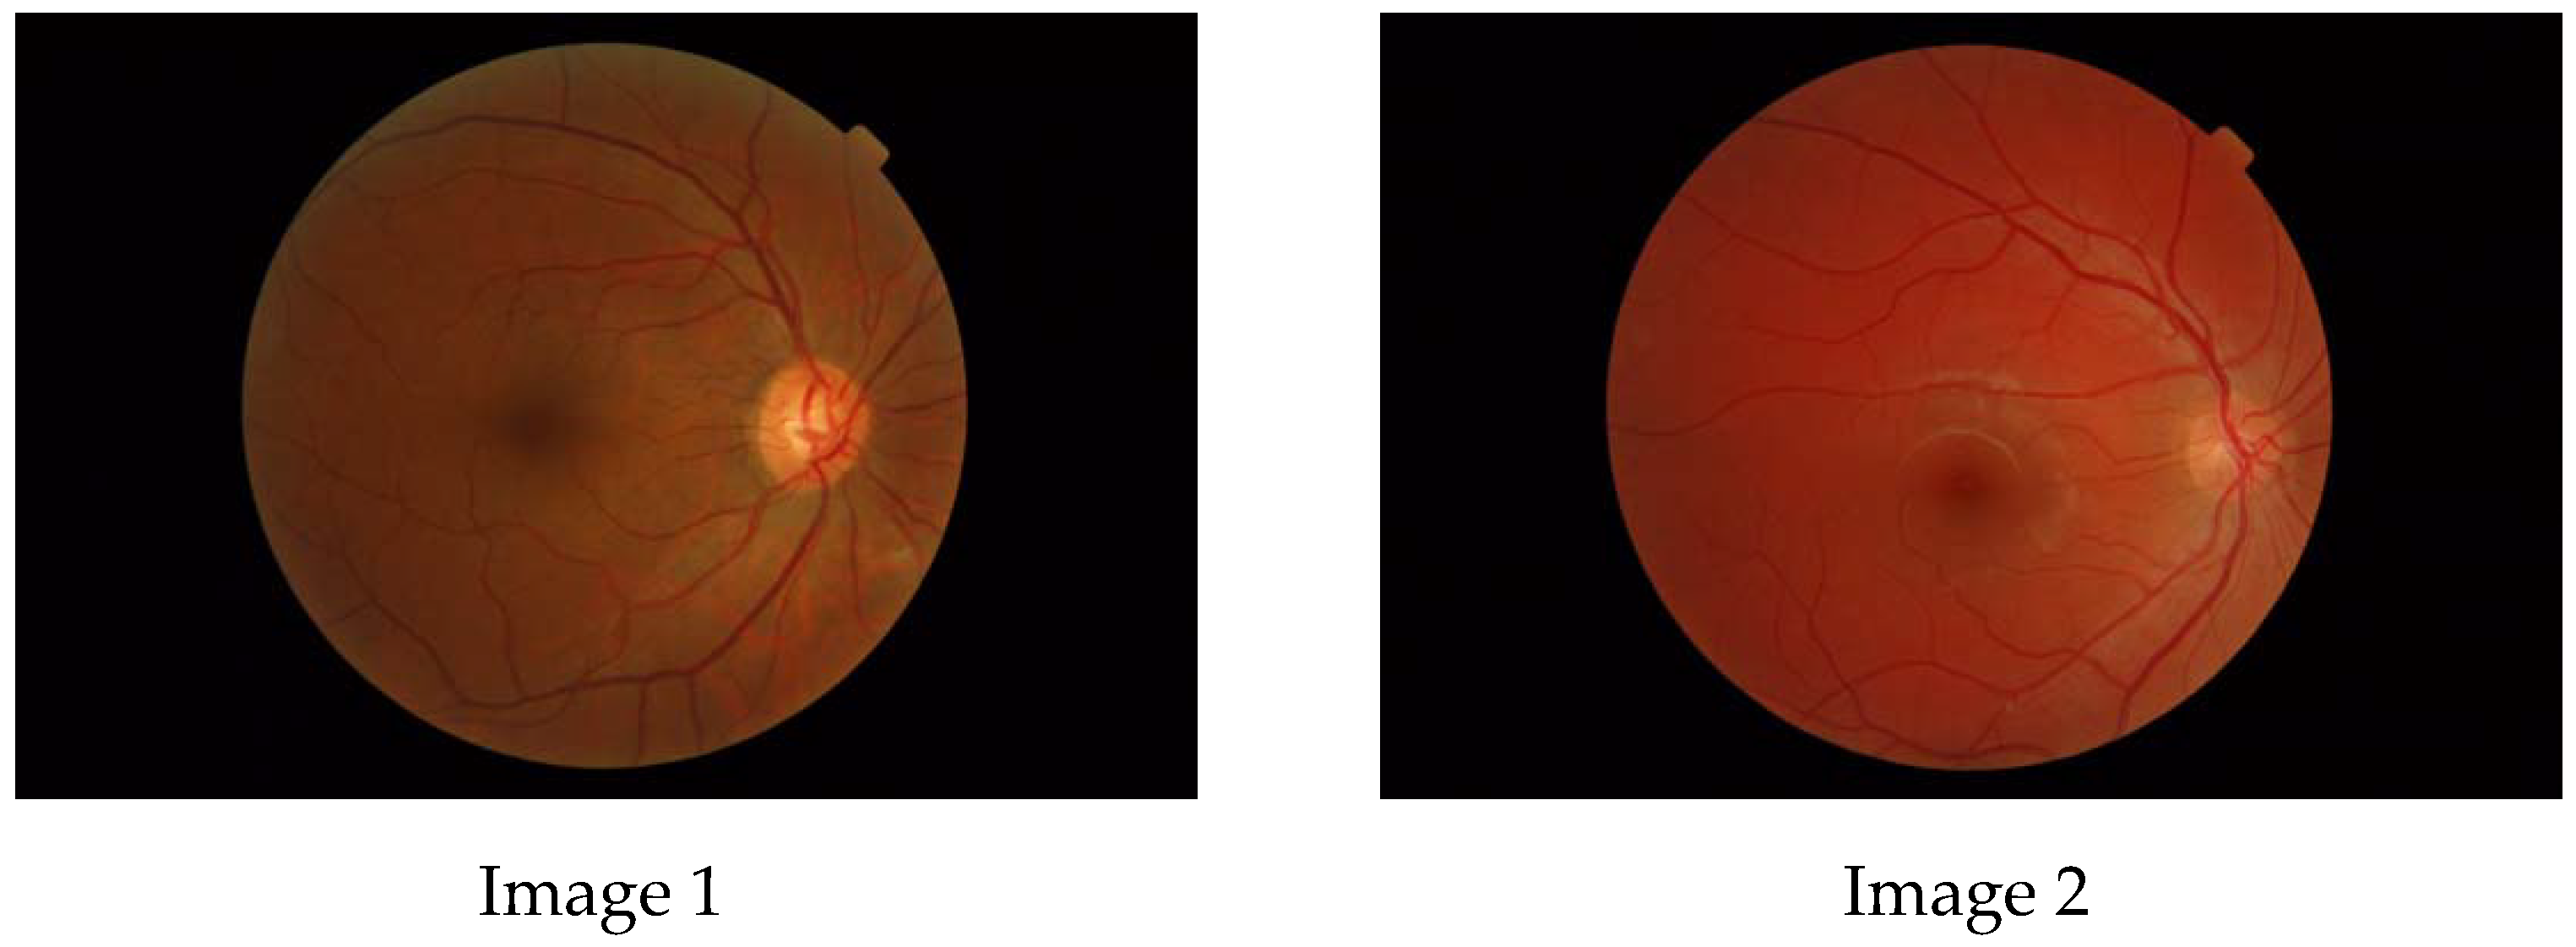

- fundus image photography;